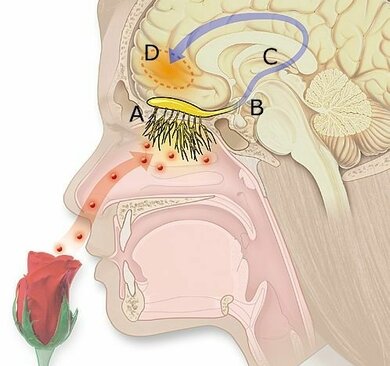

Wenn sich in der Luft, die wir einatmen, Moleküle von Geruchsstoffen befinden, können sich diese auf die Rezeptoren in der Riechschleimhaut der Nase setzen. Das löst eine Erregung des Riechnervs (Olfaktorius-Nerv) aus, der die Aktivität direkt zum Gehirn leitet. Für die Wahrnehmung von Gerüchen ist aber nicht nur das Riechsystem allein verantwortlich. Es besteht vielmehr ein Zusammenspiel von Geruchssinn, Geschmackssinn und Sinneswahrnehmungen über den Fühlnerv der Nase (Trigeminus-Nerv).

So riecht der Mensch: Der Duft steigt in die Nase und gelangt zur Riechschleimhaut, wo der Olfaktorius-Nerv den Reiz weiterleitet zum Gehirn